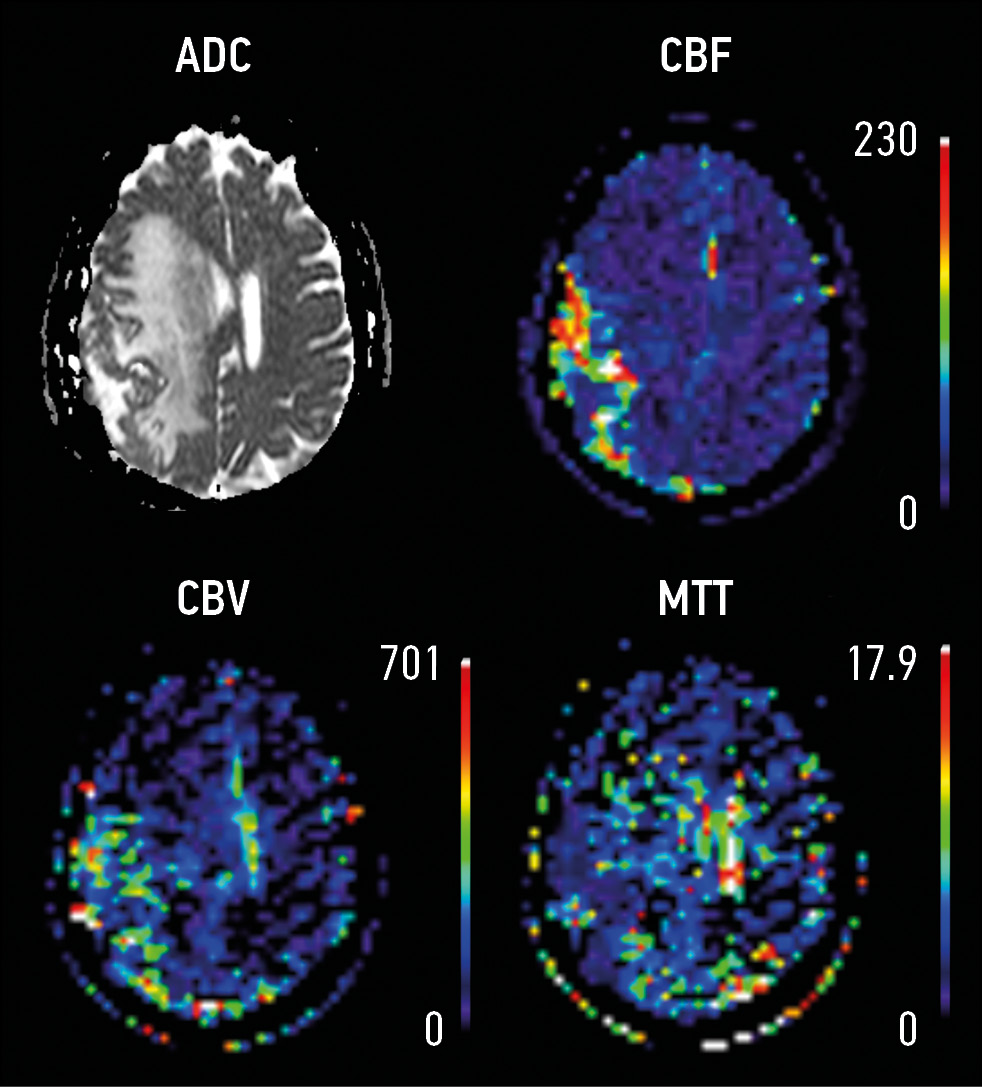

MATERIALS AND METHODS: This study retrospective analyzed the magnetic resonance imaging (1.5 T) data of 156 patients with extra-axial tumors. Patients were divided into 2 groups: Group 1 (n=106) with perifocal changes and Group 2 (n=50) with extra-axial tumors without perifocal changes. Diffusion and perfusion sequences were included in the scanning protocol. The areas of interest include (1) the lesion and (2) the area of perifocal changes. Measurements were made from the lesion and the area of perifocal changes on ACD and DSС maps, DCE was analyzed.

RESULTS: The maximum lesion size in Group 1 was 2.2 cm (1.4; 4.3), whereas in 1.2 cm in Group 2 (0.9; 3.5). In Group 1, the diffusion restriction from the lesion was detected in 42 patients (39.6%), whereas 7 (14%) in Group 2. The maximum size of perifocal changes in Group 1 was 2.85 cm (1.5; 4.7). Diffusion restriction was detected in 52 (49.1%) cases. In Group 1, patients with verified meningioma multivariable linear regression analysis showed 3.3-times increase of rCBF of the maximum size of the lesion from the area of perifocal changes (βcoef. 3.3, CI: 1.27; 5.28), p=0.003; however, it demonstrated a 4-time decrease of rCBF (βcoef. 4 CI: -7.46; -0.71), p=0.02.

CONCLUSIONS: Perfusion and diffusion methods combined with anatomical sequences show potential use as radiomic markers for diagnostic assessment and treatment of extra-axial tumors. Further detection of radiomic functional markers from the area of perifocal changes has potential.